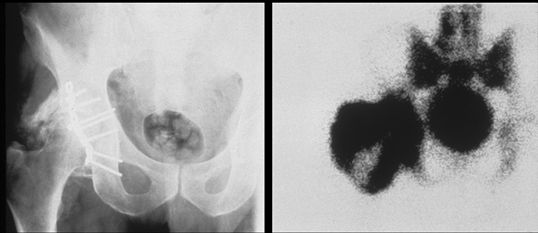

SI capsular bridging has been described in patients with

DISH, which on the pelvic anteroposterior radiograph may give the false appearance of obliteration of the SI joint space